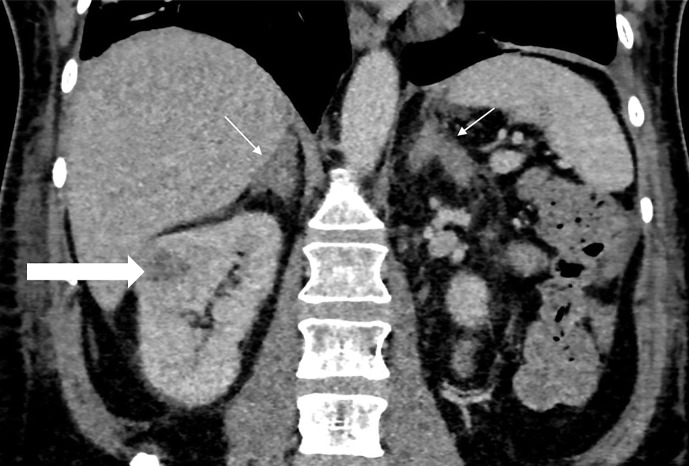

Case presentation: A 51-year-old man presented with profound hypokalemia, cellulitis, and new-onset type 2 diabetes and hypertension with 1 month of muscle weakness, labile mood, and insomnia. CS due to ectopic ACTH production was confirmed. Biochemical control was achieved using a "block-and-replace" regimen with dual blockade with ketoconazole and metyrapone and hydrocortisone replacement in addition to mineralocorticoid receptor blockade using spironolactone. CT and ultrasound demonstrated a 24 mm right renal lesion with features concerning for renal cell carcinoma. Right laparoscopic nephrectomy was performed. Histology demonstrated a WHO grade one NEN with ACTH staining.